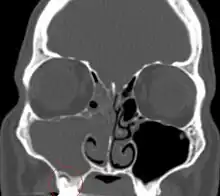

Sinusitis

Sinusitis is inflammation of the paranasal air sinuses. Odontogenic sinusitis is that which results of dental disease, most often resulting from prior dentoalveolar procedures, infections of maxillary dentition, or maxillary dental trauma.[6] Infections associated with teeth may be responsible for approximately 20% of cases of maxillary sinusitis.[7] The cause is usually a periapical or periodontal infection of a maxillary posterior tooth, where the inflammatory exudate has eroded through the bone superiorly to drain into the maxillary sinus. Treatment of the underlying dental disease is the first step in the treatment of odontogenic sinusitis, however recent a portion require endoscopic sinus surgery for successful resolution.[6] Once an odontogenic infection involves the maxillary sinus, it is possible that it may then spread to the orbit or to the ethmoid sinus.[7]